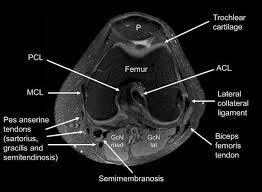

Click now to learn more about the bones, muscles, and soft tissues of these regions at leg and knee anatomy: Any tightness or weakness in the muscles around the knee makes you prone. Click on the links to show each structure. View of the anatomical labels. Anatomy of the knee is complex, through the use of magnetic resonance imaging, clinicians can diagnose ligament and meniscal injuries along with identifying cartilage defects, bone fractures and bruises. Learn anatomy using a full pacs! Knee anatomy wolfgang fitz, md jeffrey lange, md dr. In the knee mri mastery courses, we give you everything you need in order to evaluate this joint. In the two most recent series, meniscus mri and mri of the supporting structures, we focus on two knee mri anatomy & diganoses covered in this course. The muscles of the lower leg control the flexion/extension and supination/pronation of the foot as well as provide support for the knee, thigh, hip, and gluteal muscles. Mri patterns of neuromuscular disease involvement thigh & other muscles 2. The muscles of the knee include the quadriceps, hamstrings, and the muscles of the calf. Want to learn more about it?

Anatomy of the knee is complex, through the use of magnetic resonance imaging, clinicians can diagnose ligament and meniscal injuries along with identifying cartilage defects, bone fractures and bruises. Although not dangerous, can cause pain if exposure increases 50. Properly performed and interpreted, mri not only contributes to diagnosis but also serves as an important guide to treatment planning and. General anatomy and musculoskeletal system. Normal mr imaging anatomy of the knee. View of the anatomical labels. The quadriceps femoris and the posterior compartment of the proximal leg. Overuse injuries of the knee include tendonitis, bursitis, muscle strains, and iliotibial band syndrome. They move when you do—when you walk, run, dance, stretch your legs, or make any action you can think of that there are two muscle groups that act on the knee joint: The muscles of the lower leg control the flexion/extension and supination/pronation of the foot as well as provide support for the knee, thigh, hip, and gluteal muscles. Tendons attach the muscles to each other. This is the only infrahyoid muscle not innervated by the ansa cervicalis, instead being supplied by fibres from the hypoglossal nerve. Master leg and knee anatomy using our topic page.